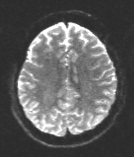

We compare the results of PyHySCO using GN-PCG, ADMM, and LBFGS on both GPU and CPU architectures. Table 3 shows the runtimes and correction quality of each optimizer on CPU and GPU. All optimizers achieve a similar correction quality with respect to relative improvement of image distance, loss value, and smoothness regularizer value, but GN-PCG has faster runtime on both CPU and GPU. On real data, GN-PCG took 10-13 seconds on average on GPU and 27-31 seconds on average on CPU, while ADMM took 11-15 seconds on GPU and 98-158 seconds on CPU, and LBFGS took 23-36 seconds on GPU and 104-141 seconds on CPU. Table 4 shows optimization metrics, including the number of iterations, stopping criteria, number of function evaluations, number of Hessian evaluations, and number of inner iterations if applicable. Consistent with its faster runtime, optimization with GN-PCG achieves a similar loss value with less computation as measured by function and Hessian evaluations. Figures 7, 8, and 9 show the field map and corrected images for each optimizer for one example subject from each dataset. The field maps and corrected images are visually similar across optimizers.

Table 6 reports the runtime and correction quality for PyHySCO using GN-PCG, HySCO, and TOPUP. On real 3T and 7T data, PyHySCO achieves lower loss and higher relative improvement between corrected images than HySCO, and higher relative improvement than TOPUP. The runtime on CPU for real data is 1-2 minutes for HySCO and over 1 hour for TOPUP, while PyHySCO on GPU has runtimes of 10-13 seconds. For the simulated dataset, PyHySCO requires an average of 1 minute on GPU, HySCO an average of 12.6 minutes on CPU, and TOPUP an average of 8.5 hours on CPU. Using the ground truth field maps from the simulated dataset, PyHySCO achieves the lowest average field map relative error, 14.48%, compared to 19.70% for HySCO and 16.36% for TOPUP. Figures 7, 8, and 9 show the field map and corrected images for one example subject from each dataset. The results of the methods are similar, and the resulting field maps are comparable to those of the existing tools, HySCO and TOPUP, while PyHySCO is considerably faster.

Refer to captionRefer to captionRefer to caption+vsubscript𝑣\mathcal{I}_{+v}inputRefer to captionRefer to captionRefer to captionPyHySCO (LBFGS)Refer to captionRefer to captionRefer to captionPyHySCO (GN)Refer to captionRefer to captionRefer to captionPyHySCO (ADMM)Refer to captionRefer to captionRefer to captionvsubscript𝑣\mathcal{I}_{-v}Refer to captionRefer to captionRefer to captionRefer to captionRefer to captionRefer to captionRefer to captionRefer to captionRefer to captionRefer to captionRefer to captionRefer to caption|+vv|subscript𝑣subscript𝑣|\mathcal{I}_{+v}-\mathcal{I}_{-v}|Refer to captionRefer to captionRefer to captionRefer to captionRefer to captionRefer to captionRefer to captionRefer to captionRefer to captionRefer to captionRefer to captionRefer to captionfield map 𝐛𝐛\mathbf{b}Refer to captionRefer to captionRefer to captionRefer to captionRefer to captionRefer to captionRefer to captionRefer to captionRefer to caption+vsubscript𝑣\mathcal{I}_{+v}TOPUPRefer to captionRefer to captionRefer to captionHySCORefer to captionRefer to captionRefer to captionvsubscript𝑣\mathcal{I}_{-v}Refer to captionRefer to captionRefer to captionRefer to captionRefer to captionRefer to caption|+vv|subscript𝑣subscript𝑣|\mathcal{I}_{+v}-\mathcal{I}_{-v}|Refer to captionRefer to captionRefer to captionRefer to captionRefer to captionRefer to captionfield map 𝐛𝐛\mathbf{b}Refer to captionRefer to captionRefer to caption